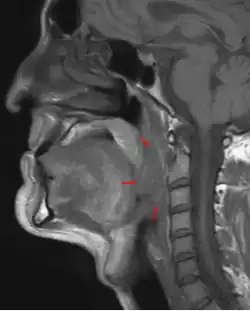

Oropharyngeal cancer

Oropharyngeal cancer,[1][2][3] also known as oropharyngeal squamous cell carcinoma and tonsil cancer,[1] is a disease in which abnormal cells with the potential to both grow locally and spread to other parts of the body are found in the oral cavity, in the tissue of the part of the throat (oropharynx) that includes the base of the tongue, the tonsils, the soft palate, and the walls of the pharynx.[1][2][3][5]